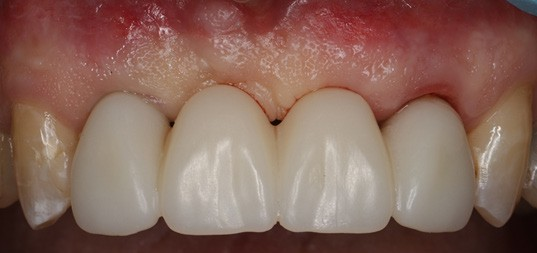

Once the temporary is picked up and emergence profile is customized to have an adequate regenerative space and properly placed Critical contour (0.5 short of the final gingival margin) we are ready to deliver the prosthesis.

Prior to delivery make sure to leave a good amount of room in the embrasures to allow for soft tissue fill during the training period.

Upon delivery of the prosthesis, some blanching is a good sine of tissue compression in needed areas (usually proximally) which starts the process of tissue training.

After 3 months of tissue training, patient returned for his final evaluation prior to final restoration.